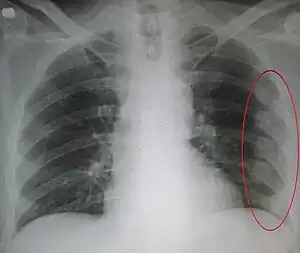

A fratura na costela é a quebra de um dos ossos da costela.[1] Isto normalmente resulta em dor no peito que piora com a respiração. Hematomas podem ocorrer no local da quebra.[3] Quando várias costelas estão quebradas em vários lugares resulta em um tórax instável.[4] Complicações potenciais incluem um pneumotórax, contusão pulmonar e pneumonia.

As fraturas de costelas ocorrem, geralmente, a partir de um golpe direto no peito, como durante uma colisão de veículo motorizado ou a partir de um esmagamento. Tosse ou câncer metastático pode também resultar em uma costela quebrada. A parte meio das costelas são mais frequentemente fraturadas.[5] As fraturas da primeira ou segunda costela são mais susceptíveis de serem associadas a complicações.[6] O diagnóstico pode ser feito com base nos sintomas e suportado pela geração de imagens médicas.